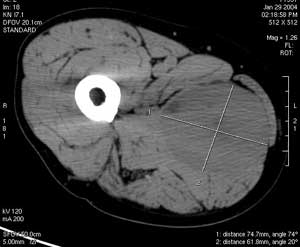

Bk8s2.jpg

(300 × 247像素,文件大小:9 KB,MIME类型:

横纹肌肉瘤